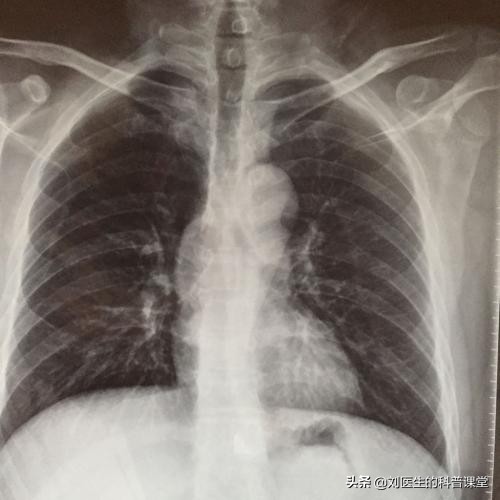

正常肺部胸片